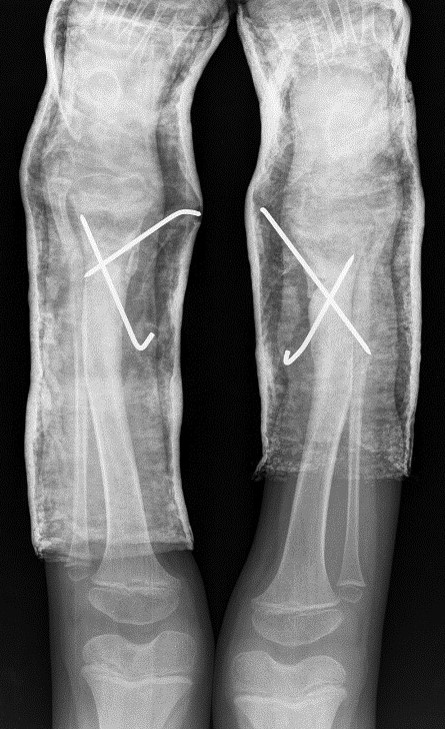

The X-ray showed a bowing of distal tibia, bilaterally, producing a varus deformity of 53 degrees (Fig. 2).

Surgical correction was scheduled. It was performed an opening wedge tibia osteotomy and filled the remaining gap with structural fibular graft. It was fixed with two crossed K-wires and cast immobilization. Both surgeries were performed at the same operative time (Figs 3 and 4).